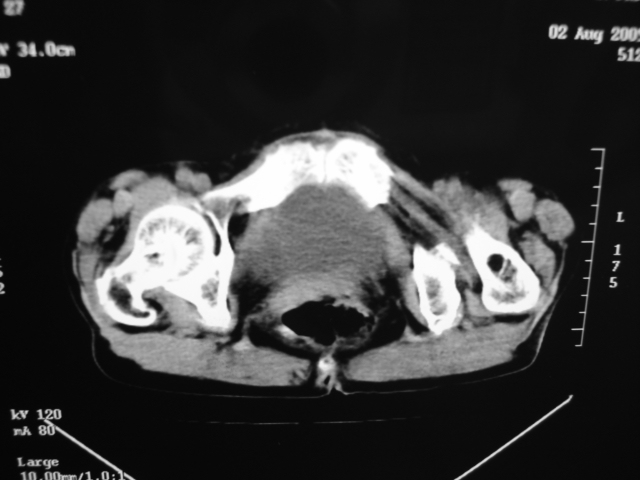

同事奶奶,73岁,腹痛一年,夜晚较重,潜血+++,拒绝增强,考虑左肾ca并腹膜后转移;请各位老师帮忙看看,谢谢!

左肾癌侵及输尿管上段,腹膜后多发淋巴结转移,脾脏钙化灶。至于潜血+++,要考虑消化道病变,本次ct片肠腔未见明显异常。

潜血+++是尿还是便?如果是便,则考虑肾癌侵犯降结肠可能。

1)考虑左肾癌侵犯肾盂并腹膜后淋巴结转移。2)脾脏钙化灶。

查查一胸部,不除外肺癌伴左侧肾上腺,腹膜后淋巴结及左肾转移.

定位像见上肺野也很糟糕,支持7楼。

考虑左肾癌侵犯肾盂并腹膜后淋巴结转移。